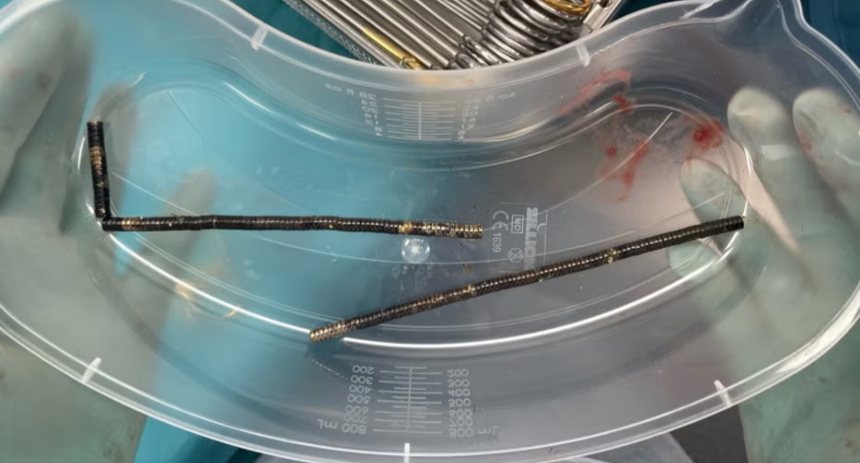

Una radiografía mostró que los imanes se habían agrupado en cuatro líneas rectas dentro de los intestinos del adolescente. «Estas parecían estar en partes separadas del intestino, adheridas entre sí debido a fuerzas magnéticas», dijeron.

Los médicos informaron que la presión de los imanes había causado necrosis (muerte del tejido) en cuatro zonas del intestino delgado y parte del intestino grueso. Los cirujanos operaron para extirpar el tejido muerto y recuperar los imanes, y el adolescente pudo regresar a casa tras ocho días de hospitalización.